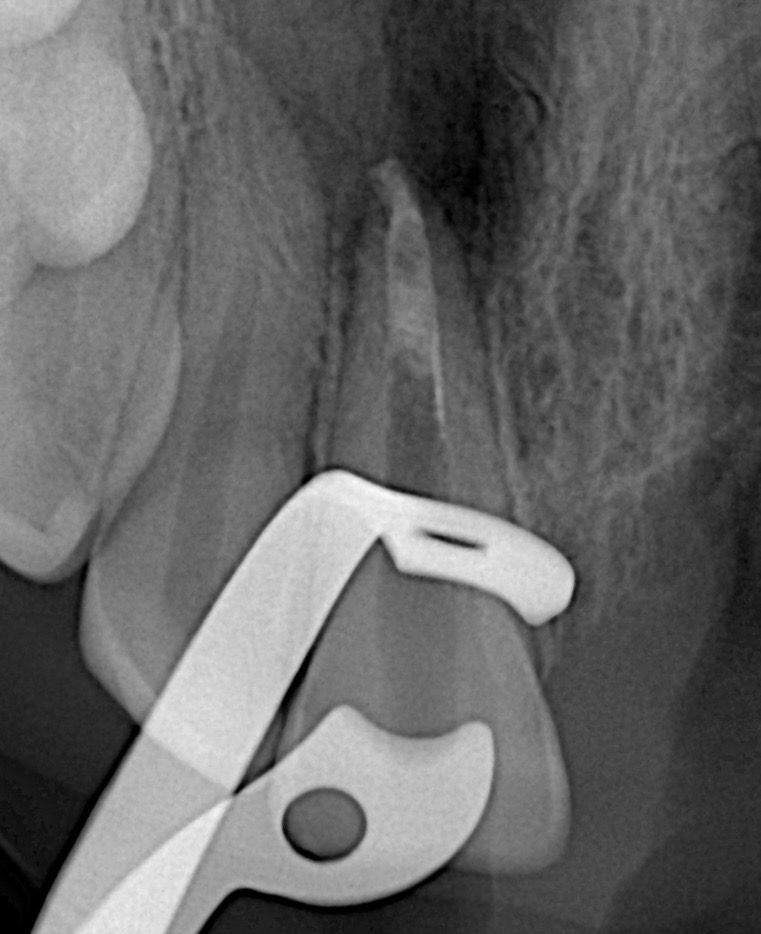

Step 4 – Apical Barrier Formation

A collagen barrier was not required due to controlled MTA delivery. ProRoot MTA was placed incrementally in the apical 4–5 mm using a micro-carrier and condensed with an MTA plugger under microscope guidance.

Step 5 – BioSeal Application

After verifying the apical barrier radiographically, BioSeal bioceramic material was used to seal the remaining canal space coronally.